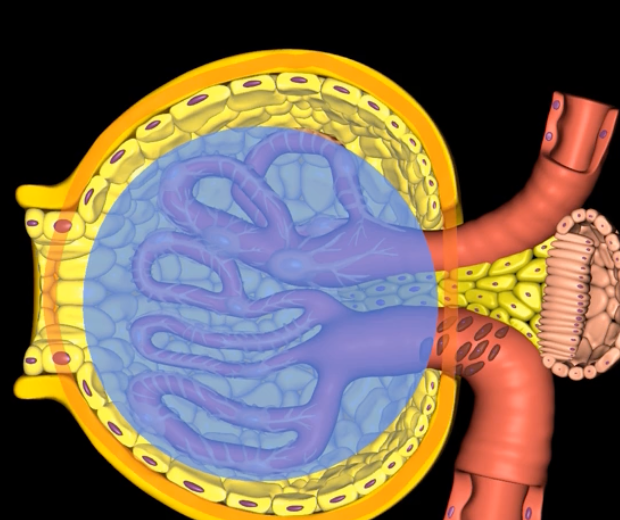

Podocytes

nephron

type of cell

Bowman’s capsule

Glomerular filtration involves pressured movement of fluid and solutes from the blood into ___ (blue arrows)

capillaries

orange

green

endothelium

filtration membrane is composed of ____ (yellow)

visceral layer of Bowman’s capsule

purple

basement membrane

blue

afferent arteriole

visceral layer

orange cells

foot processes

filtration slits/slit diaphrams

yellow

capsular space

outlined in blue

blue space